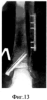

Больная Б-ц 25 лет, история болезни №3645. На улице подвернула левую стопу, почувствовала резкую боль. Доставлена машиной “СП” в 59 ГКБ. Диагноз: Закрытый надсиндесмозный перелом левой малоберцовой кости, перелом внутренней лодыжки, разрыв дистального межберцового синдесмоза с подвывихом стопы кнаружи (фиг.12, 12а). При поступлении под местной анестезией произведена ручная репозиция с наложением циркулярной гипсовой повязки “сапожок”. На контрольных рентгенограммах положение отломков неудовлетворительное.

Операция – остеосинтез перелома малоберцовой кости в нижней трети компрессирующей пластиной, остеосинтез внутренний лодыжки винтом и деротационной спицей (фиг.13 и 13а). Задняя гипсовая лонгета. Заживление послеоперационных ран без осложнений. Швы удалены через две недели. На поврежденный сегмент конечности “голень-стопа” с помощью аппарата наложена полимерная повязка – ортез, изготовленная из Scotchcast и Soft Cast. Через 2-3 часа после высыхания и затвердевания ортеза пациентка обучена ходьбе с полной нагрузкой на поврежденную конечность без дополнительной опоры. Для разработки двигательной функции поврежденного голеностопного сустава ортез по передней поверхности “рассечен”, фиксирован на поврежденной конечности самофиксирующим эластичным бинтом. Пациентка с этого периода времени периодически снимала с поврежденной конечности ортез. Через 4 недели после операции произведено укорочение ортеза по тыльной и подошвенной поверхности, чтобы фиксирующий ортез практически не мешал движениям стопы. Ношение ортеза на поврежденной конечности 8 недель. Вышла на работу через 3 недели после операции. Рентгенограммы больной через 2 года после операции (фиг 14, 14а).